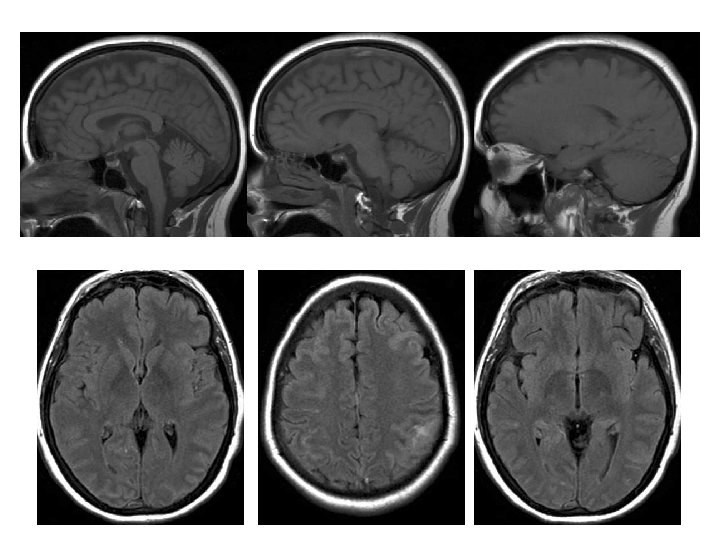

IRM • Diagnostic: – Sagittales T 1 en SE +++ – Coronales T 2 ou Flair – Axiales T 2 EG ++ +/- Coronales T 1 sans et avec Gado • Extension (et suivi) : ARM veineuse – – Contraste de phase 3 D PC Temps de vol 2 D TOF veineux Acquisition volumique +Gd ARM dynamique 42